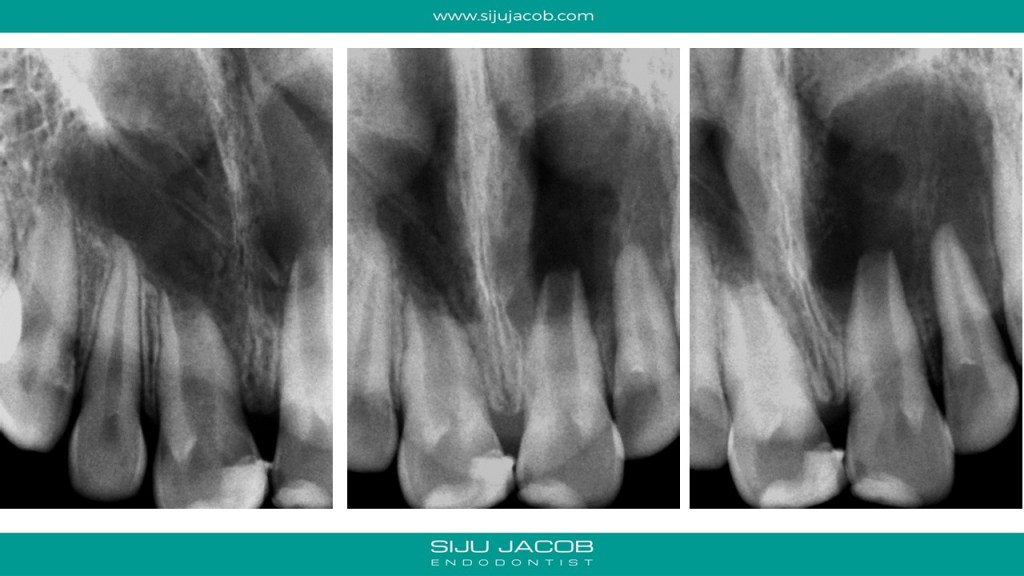

This was probably the largest lesion I ever treated. It had several interesting characteristics. It would be tough to explain with just pics. So, I made it into a short presentation